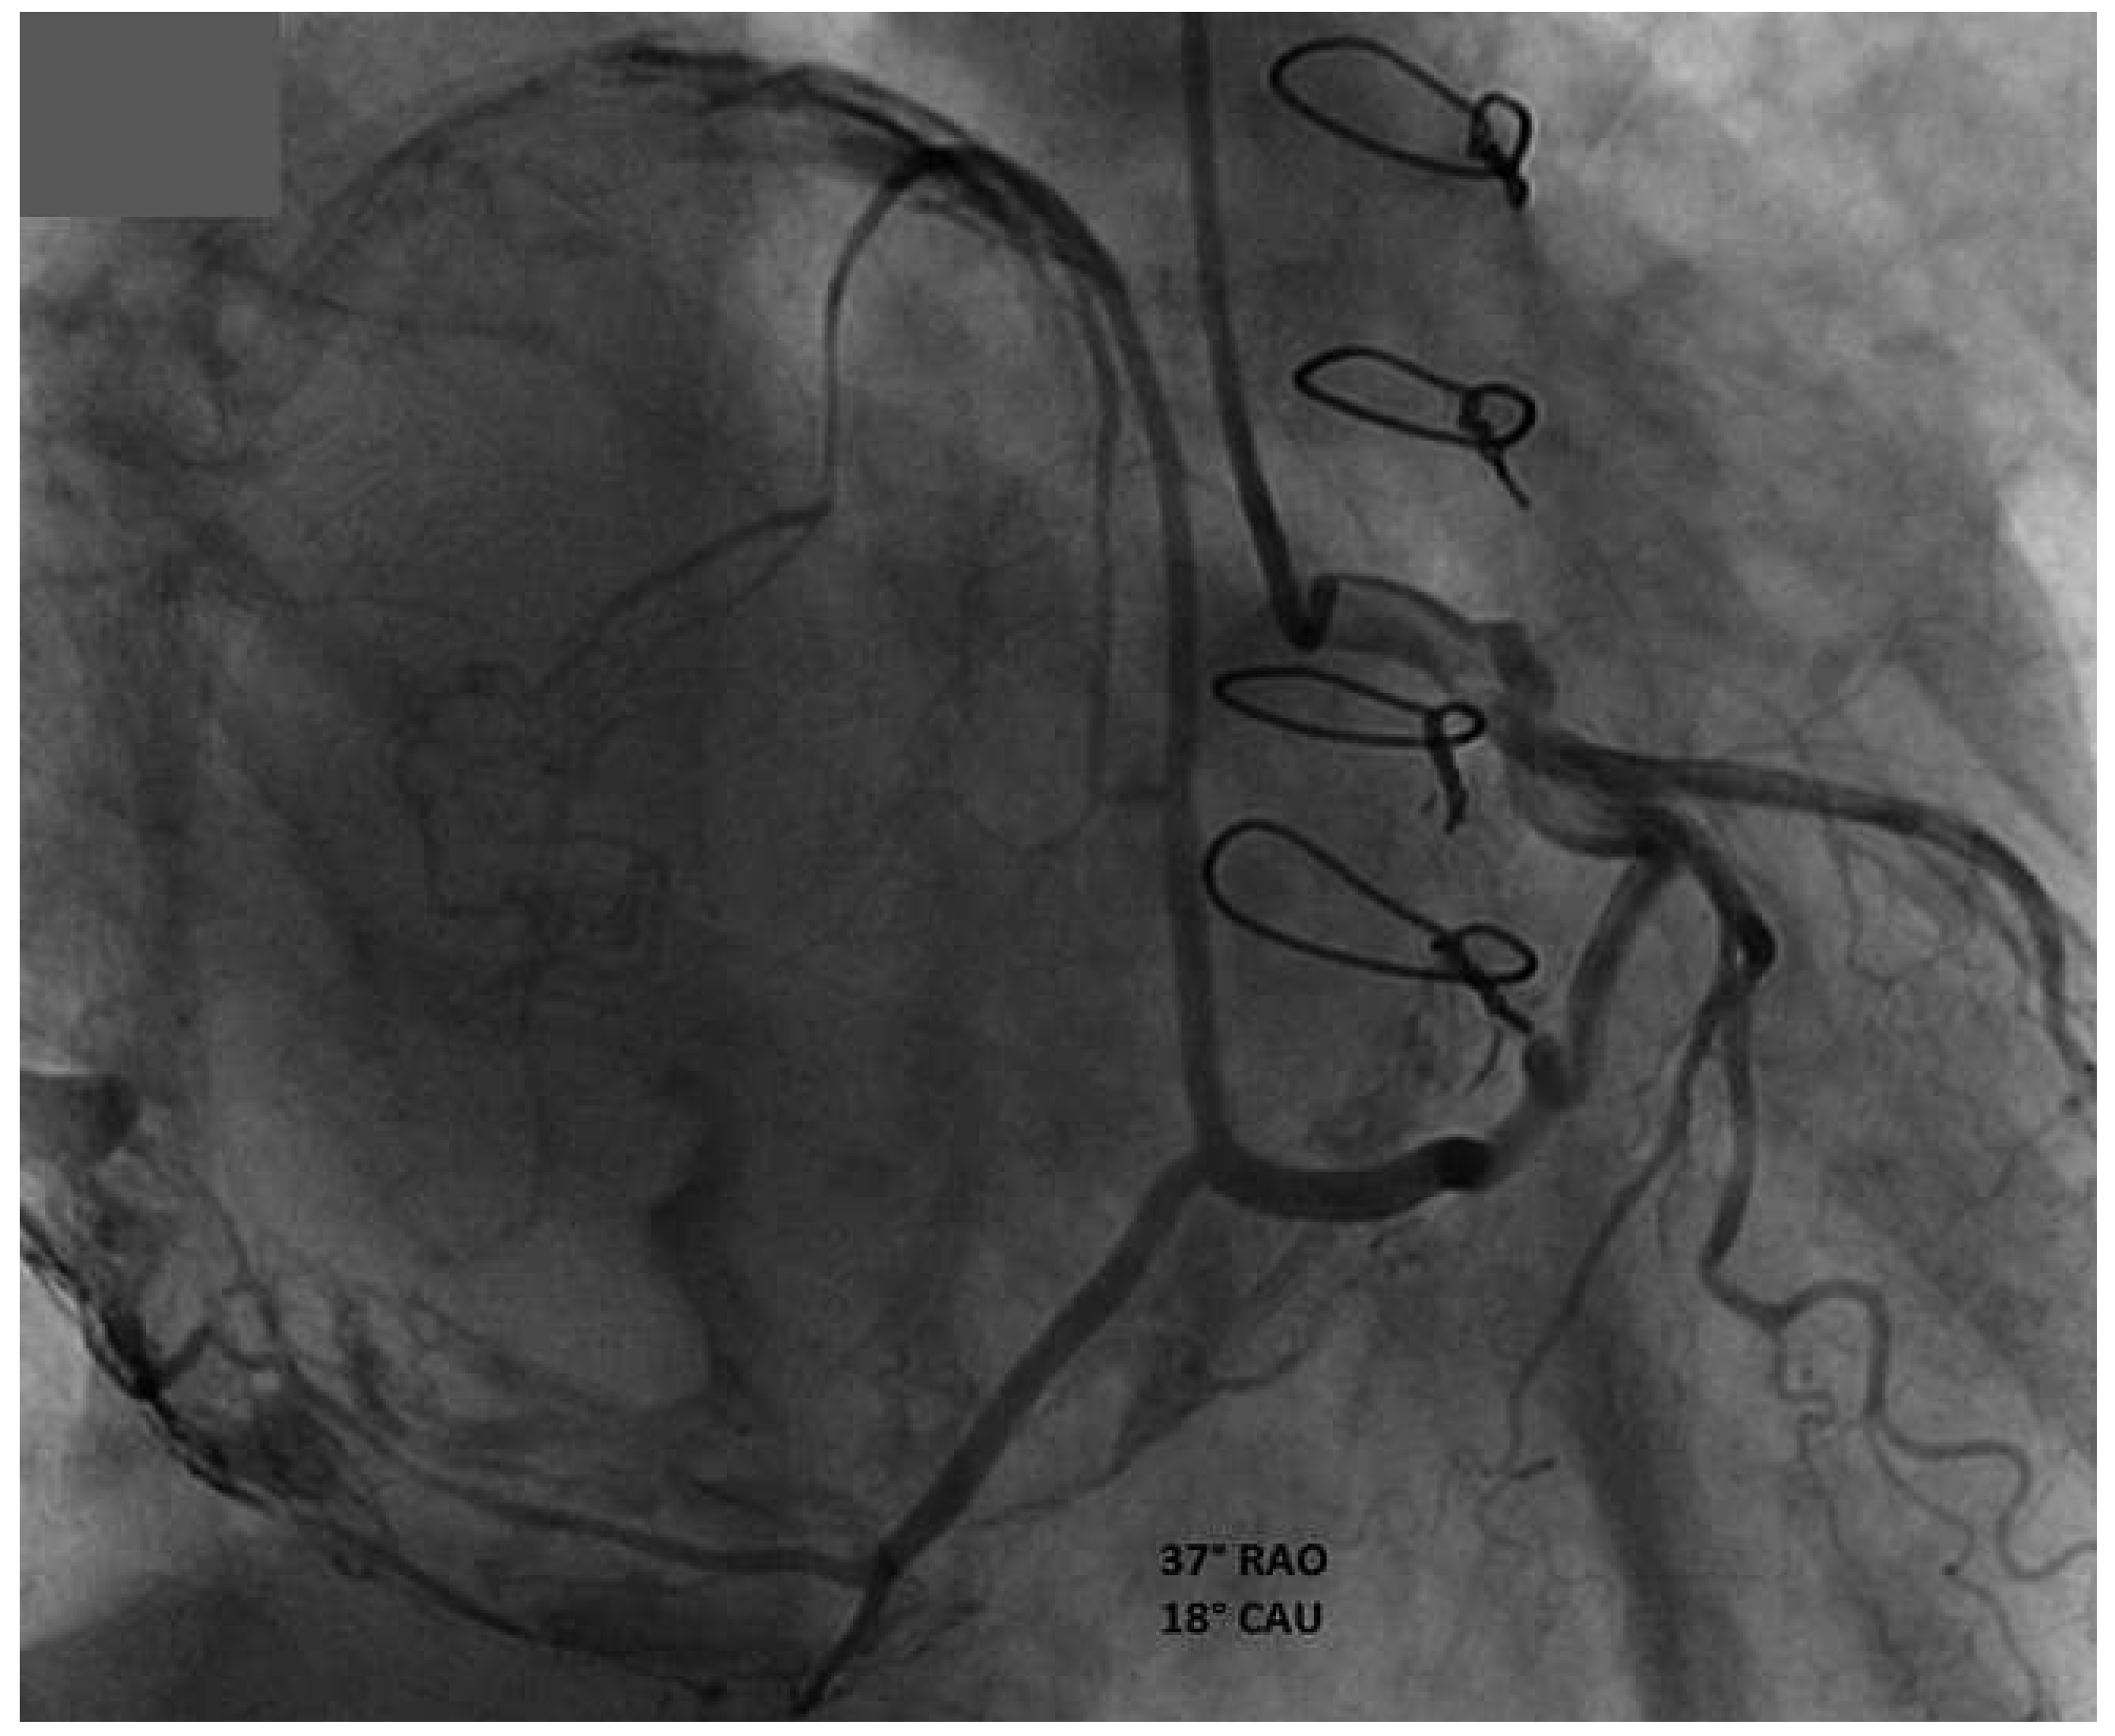

Coronary angiography revealed normal coronary arteries and showed several hypertrophic branches for the left atrium supplying blood to the two masses, with evidence of left-to-left shunt (Figure 3).

Figure 3. Angiogram of the 37°RAO–18°CAU view. This view shows several hypertrophic branches for the left atrium supplying blood to the two masses, with evidence of left-to-left shunt.